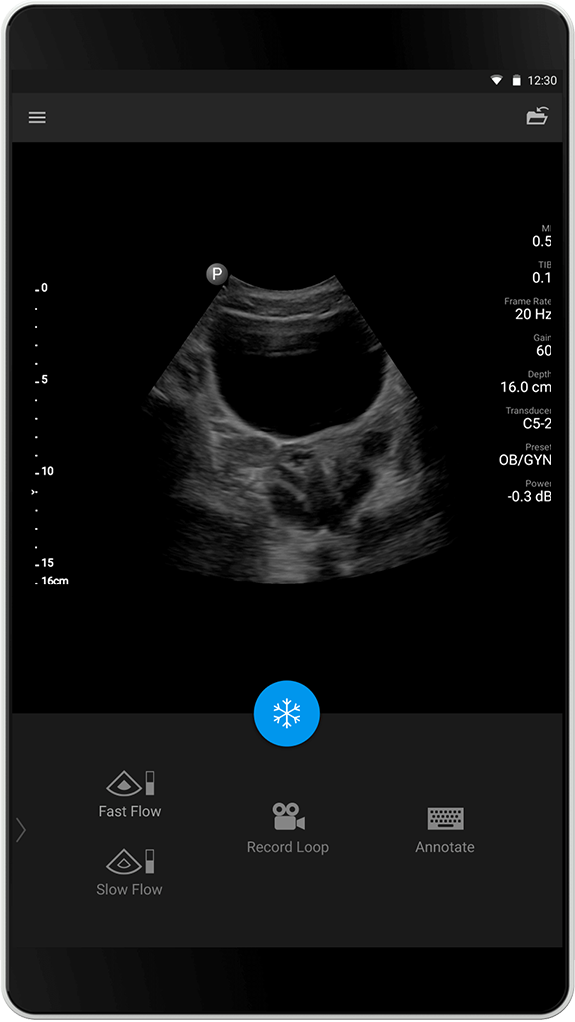

Forhåndsinnstillingen for abdomen er optimalisert for robust penetrasjon og allsidig skanning av abdomen. Optimalisering av fargedoppler i abdomen er utformet for rask fremhevning av høyere flows i abdominale arterier så vel som lavere flows i organer som nyrene.